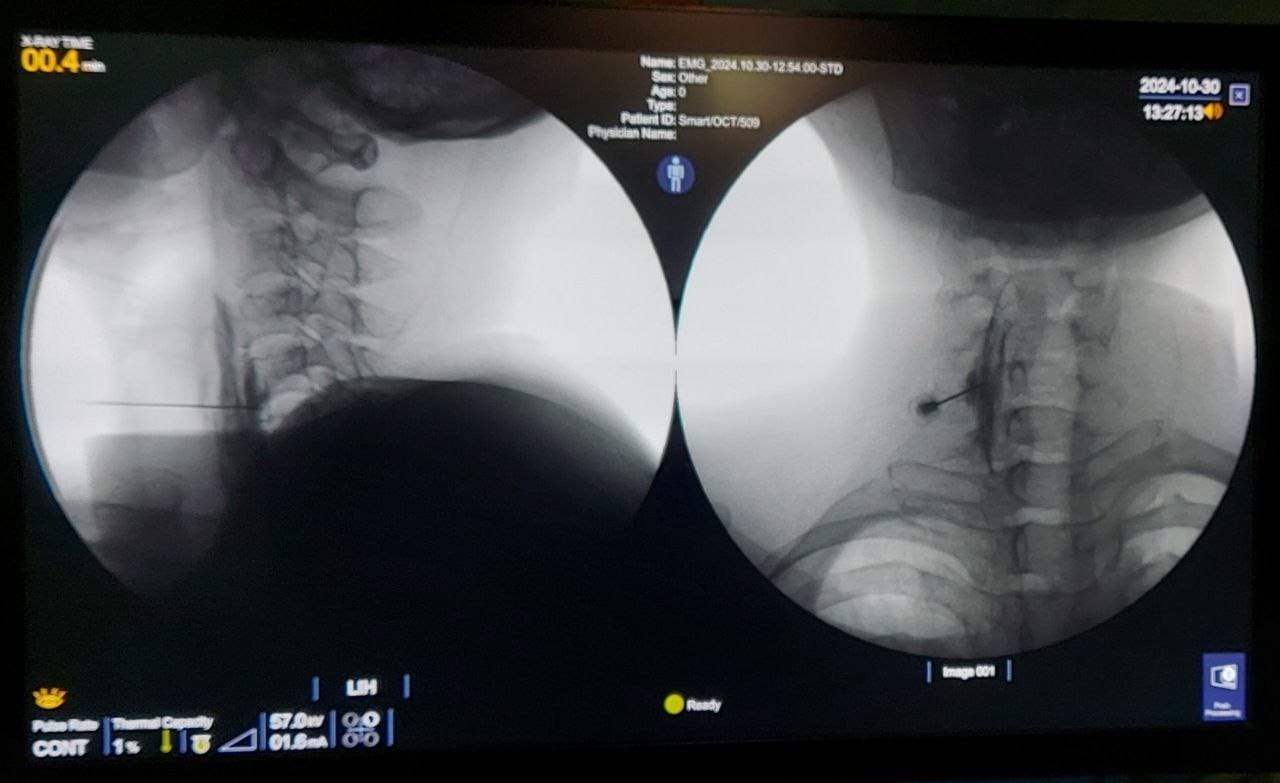

Procedures